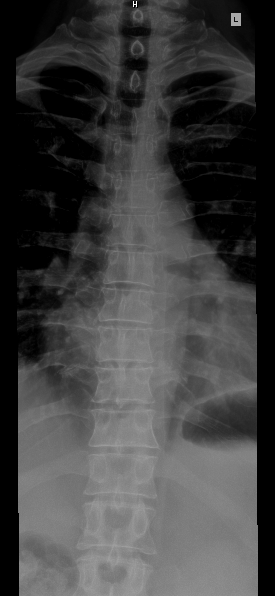

등뼈는 척추의 흉부에 위치하며, 갈비뼈와 연결되어 흉곽을 형성하는 뼈이다. 일반적인 특징으로 척추뼈몸통, 척추뼈뿌리, 척추뼈고리판, 척추뼈구멍, 가시돌기, 위관절돌기, 아래관절돌기, 가로돌기 등으로 구성된다. 각 등뼈는 흉추 신경이 지나가며, 제1등뼈, 제9~12등뼈는 다른 등뼈와 차이점을 보인다. 다른 척추동물의 흉추 수는 종에 따라 다르며, 포유류는 일반적으로 12~15개, 조류는 자유 흉추와 유합 흉추로 구분된다.

2. 일반적 특징

제2~8등뼈는 다음과 같은 공통적인 특징을 가진다. 제1등뼈와 제9~12등뼈는 약간의 차이점이 있어 별도로 기술한다.[1]

- 척추뼈몸통: 심장 모양이며, 앞뒤와 좌우 폭이 넓다. 위아래는 평평하고, 앞쪽은 좌우로 볼록하며, 뒤쪽은 오목하다. 양쪽에는 갈비뼈와 만나는 두 쌍의 반관절면이 있다.

- 척추뼈뿌리: 척추뼈몸통에서 뒤쪽, 약간 위쪽으로 향하는 구조물이며, 아래척추뼈패임이 깊고 크다.

- 척추뼈고리판: 넓고 두꺼우며 지붕의 기와처럼 겹쳐져 척수를 보호한다.

- 척추뼈구멍: 작고 둥근 모양이며, 척수가 지나간다.

- 가시돌기: 길고 삼각형 모양이며, 아래쪽으로 비스듬히 뻗어 있다. 제5~8등뼈의 가시돌기는 서로 겹쳐진다.

- 위관절돌기: 얇은 뼈판 모양이며, 위쪽으로 돌출되어 있다. 관절면은 평평하고 뒤쪽, 약간 가쪽과 위쪽을 향한다.

- 아래관절돌기: 척추뼈고리판과 융합되어 있으며, 아래쪽 가장자리에서 약간 돌출되어 있다. 관절면은 앞쪽, 약간 안쪽과 아래쪽을 향한다.

- 가로돌기: 위관절돌기와 척추뼈뿌리 뒤쪽에서 시작되며, 두껍고 강하며 뒤쪽과 가쪽으로 비스듬히 뻗어 있다. 끝은 뭉툭하고 갈비뼈 결절과 관절하는 오목한 면이 있다.